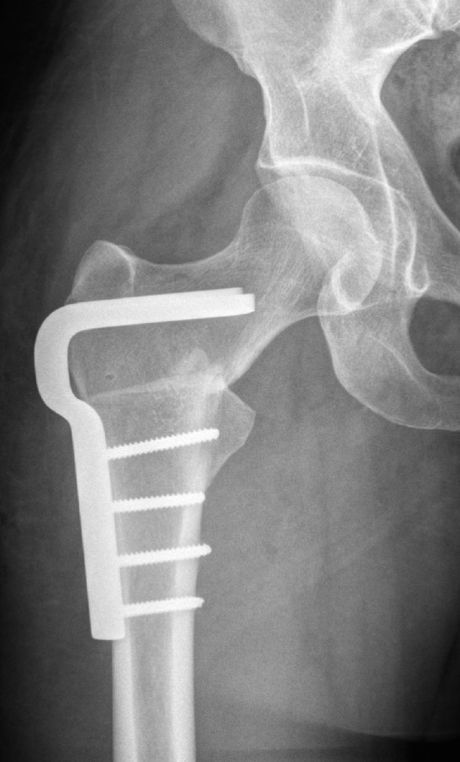

Proximale Femur Osteotomie (PFO, VDRO, Korrektur der. Beinachse am oberen Oberschenkel)